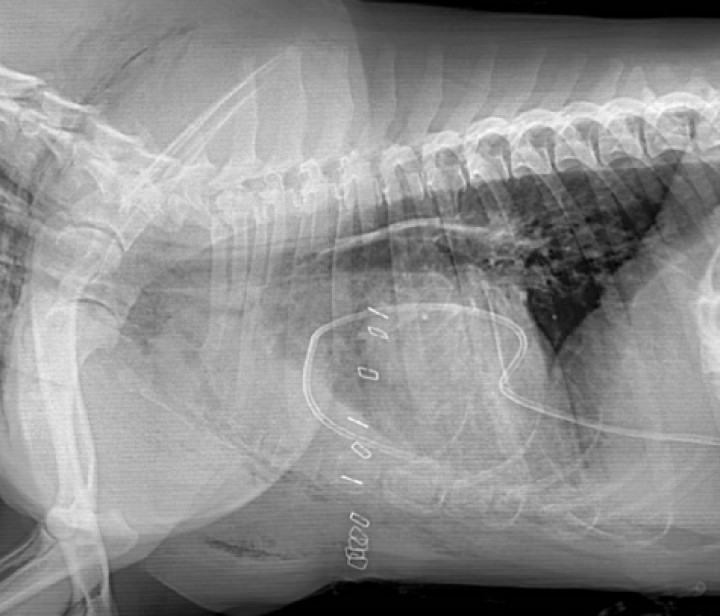

En ambas proyecciones se observa un aumento de la radiodensidad en la entrada de la cavidad torácica, y múltiples estructuras de diferente forma y tamaño, radiopacas con densidad hueso en el abdomen craneal, en el área del estómago. En la proyección lateral derecha, a nivel de la primera y segunda costilla, se observa una estructura radiopaca, con densidad de hueso. Craneal a esta zona se observa acúmulo de gas y dilatación esofágica y, caudalmente, se observa radiodensidad de tipo gas y tejido blando (posiblemente líquido) (Fig. 2).

<p>Misma imagen que la Figura 1. (<strong>A</strong>) Radiografía de la cavidad torácica. A nivel de la entrada torácica, se observa una zona con aumento de la opacidad, con densidad hueso (flecha gruesa), el esófago craneal a esta zona está dilatado con acúmulo de gas (flecha fina). En abdomen craneal, se observan en estómago estructuras de distinta forma y tamaño con radiopacidad hueso (asterisco). (<strong>B</strong>) Aumento de la densidad radiográfica en la entrada torácica con aumento de las dimensiones del mediastino craneal (flecha). El estómago contiene numerosas estructuras con densidad hueso (asterisco).</p>

Figura 2

Misma imagen que la Figura 1. (A) Radiografía de la cavidad torácica. A nivel de la entrada torácica, se observa una zona con aumento de la opacidad, con densidad hueso (flecha gruesa), el esófago craneal a esta zona está dilatado con acúmulo de gas (flecha fina). En abdomen craneal, se observan en estómago estructuras de distinta forma y tamaño con radiopacidad hueso (asterisco). (B) Aumento de la densidad radiográfica en la entrada torácica con aumento de las dimensiones del mediastino craneal (flecha). El estómago contiene numerosas estructuras con densidad hueso (asterisco).